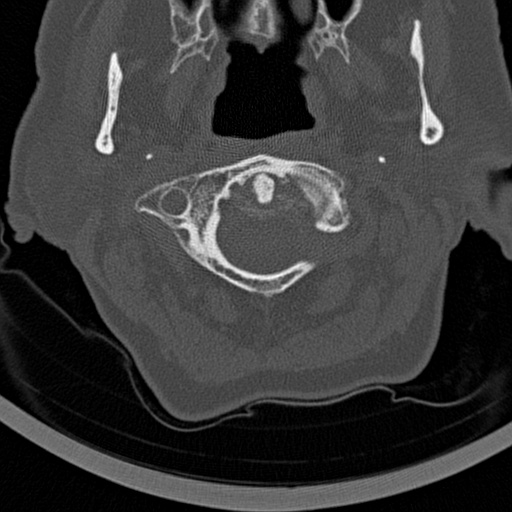

Overall The preprocessing phase for preparing images to be used in an image classification notebook is showcased by Algorithm 1, with selected outputs depicted in Figure 4.